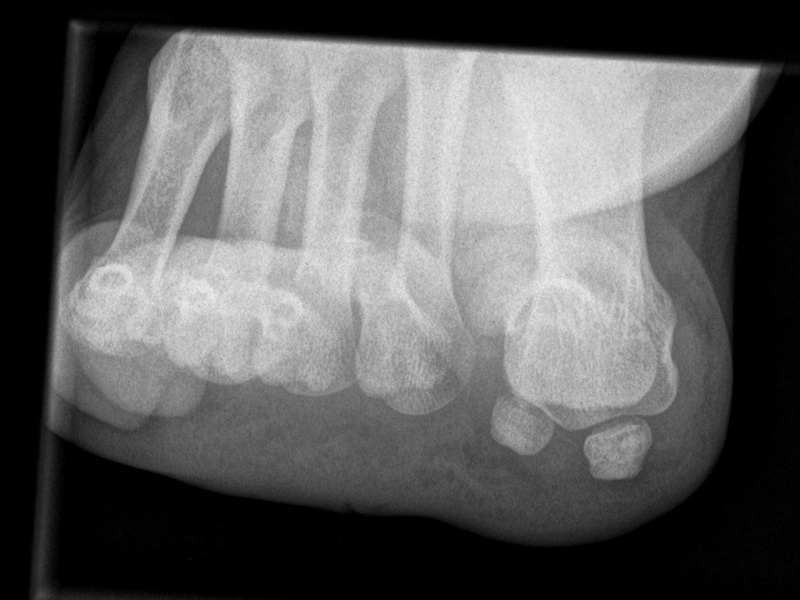

Fuß schräg ohne Belastung (45° Pronationsaufnahme)

Positionierung:

• Der Patient sitzt auf dem Untersuchungstisch.

• Der Fuß steht auf der Kassette, der laterale Fußrand wird um 45° angehoben (optional Verwendung eines Keilkissens).

• Der Zentralstrahl wird auf das Tarsometatarsalgelenk III zentriert.

• Die Röhre ist 0° vertikal ausgerichtet.

Kennzeichen des Röntgenbildes:

• Überlagerungsfreie Darstellung der Zehen und Mittelfussknochen, sowie eine gute Beurteilbarkeit der Fusswurzelknochen.

• Knochenbrücken der Fußwurzelknochen (z.B. Coalitio calcaneonaviculare) lassen sich mit dieser Aufnahme gut darstellen.

• Der Weichteilmantel ist erkennbar.

• Die 45° Pronationsaufnahme wird häufig als dritte Ebene mit belasteten Aufnahmen seitlich und dorsoplantar angefertigt.

Besondere Bemerkungen zum Beispielbild:

• Der Patient erlitt ein Mittelfußtrauma. Unter Frakturverdacht erfolgten die unbelasteten Aufnahmen.

• In der schrägen Aufnahme ist die Frakturlinie im Os cuneiforme I am besten erkennbar.

• Unauffällige Abbildung des restlichen Fußskeletts.

• Für die OP-Planung erfolgte dann noch ein Schnittbildverfahren.